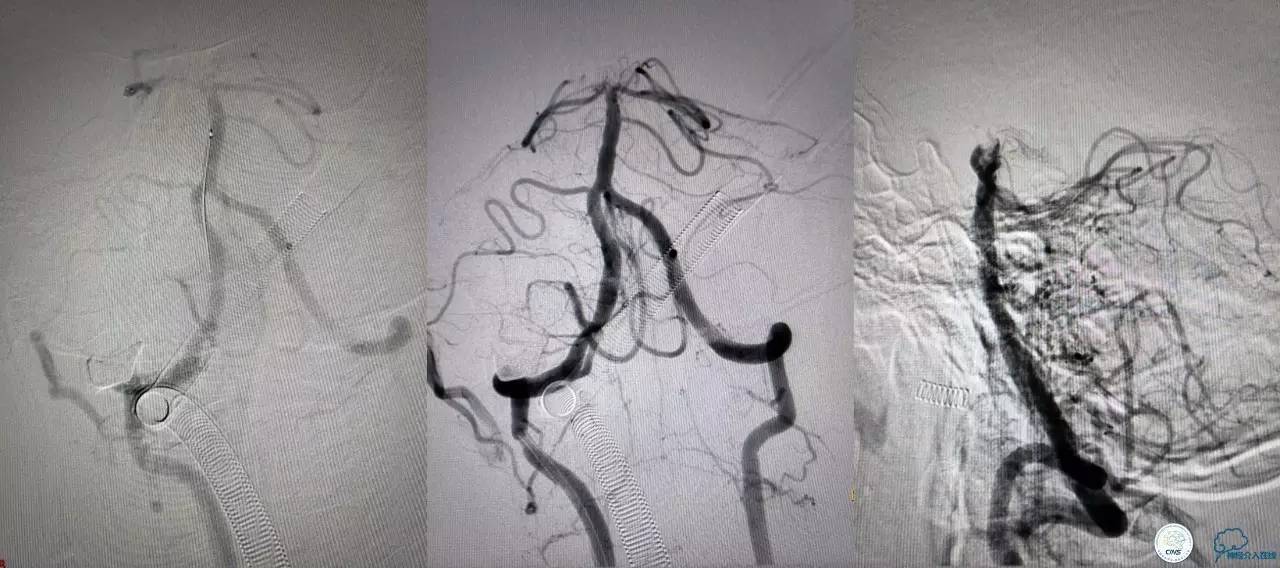

好大的血栓,支架释放后,血管无复流,拉一把!

没错,没看错!血管成功实现再通,术中取栓的栓子如下。

术后生命体征平稳,成功撤呼吸机,肌力较前好转,复查头颅CT:

右侧丘脑高密度影,右侧枕叶可能也有梗死,祈祷慢慢恢复吧!